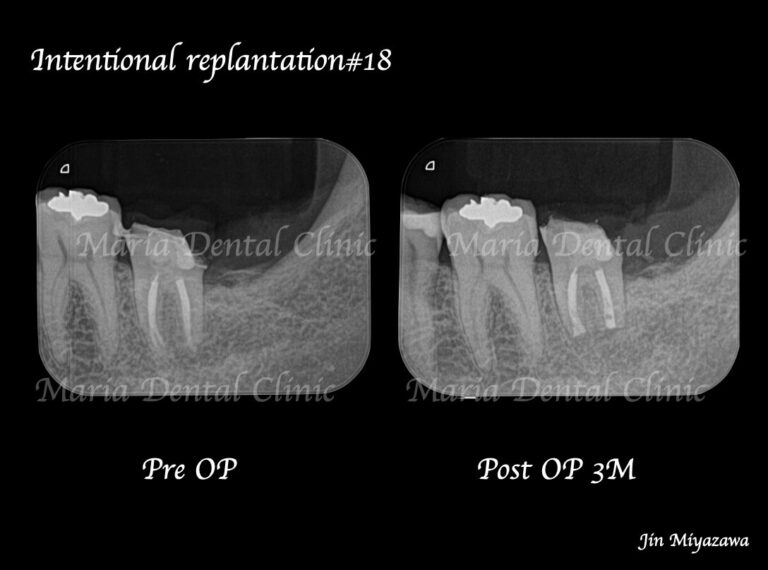

• 目白マリア歯科【症例】根管治療後も症状の改善が認められないケース・意図的再植・歯根端切除術レントゲン画像術前術後

【症例】根管治療後も症状の改善が認められないケース・歯根端切除術(意図的再植術)を施し治癒へ